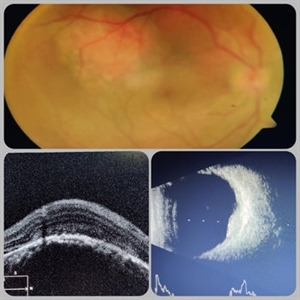

Multimodal Imaging in CHRPE

Multimodal Imaging in CHRPE

Mar 6 2025 by Gerardo - Montante Montelongo, MD

Fundus photograph of an 83-year-old male with a history of Diabetes, smoking, cataract surgery on the right eye in 2022, and open-angle glaucoma. Asymptomatic. Indirect ophthalmoscopy revealed 80% excavation, peripapillary atrophy, and a hyperpigmented perifoveal lesion with 35% atrophy, 10% drusen, and 5.1 mm diameter, corresponding to a CHRPE. At multimodal imaging, FFA shows hypoautofluorescence of the lesion, OCT shows preservation of internal retinal layers, atrophy of external retinal layer, with an RPE disruption, and posterior shadowing. USG shows a flat hyperechoic lesion 5.1 mm in diameter and 1.32 mm in thickness, solid and with high internal reflectance.

Photographer: Gerardo Montante-Montelongo, MD, Mexican Institute of Ophthalmology

Imaging device: Clarus 700

Condition/keywords: congenital hypertrophy of the retinal pigment epithelium (CHRPE), multimodal imaging